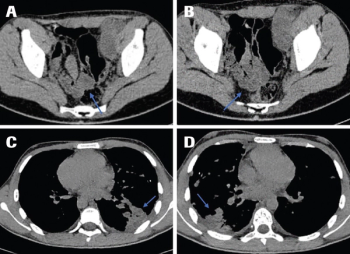

ByIrina Melnichenko, MD,Lilit Sargsyan, MD,Karen Bedirian, MPH,Davit Dallakyan MD, PhD,Artak Gevorgyan, MD,Gevorg Aloyan, MD, PhD,Artur Harutyunyan, MD,Levon Davtyan, MD,Armine Lazaryan, MD,Narek Manukyan, MD,Gevorg Tamamyan, MD, Phd, MSc,Ruzanna Papyan, MD A systematic review of reported clinical cases and treatment strategies was performed to better understand the prognostic factors and to develop the best possible treatment option for a 16-year-old patient diagnosed with a malignant triton tumor in the lower extremity with distant metastases in the lungs.